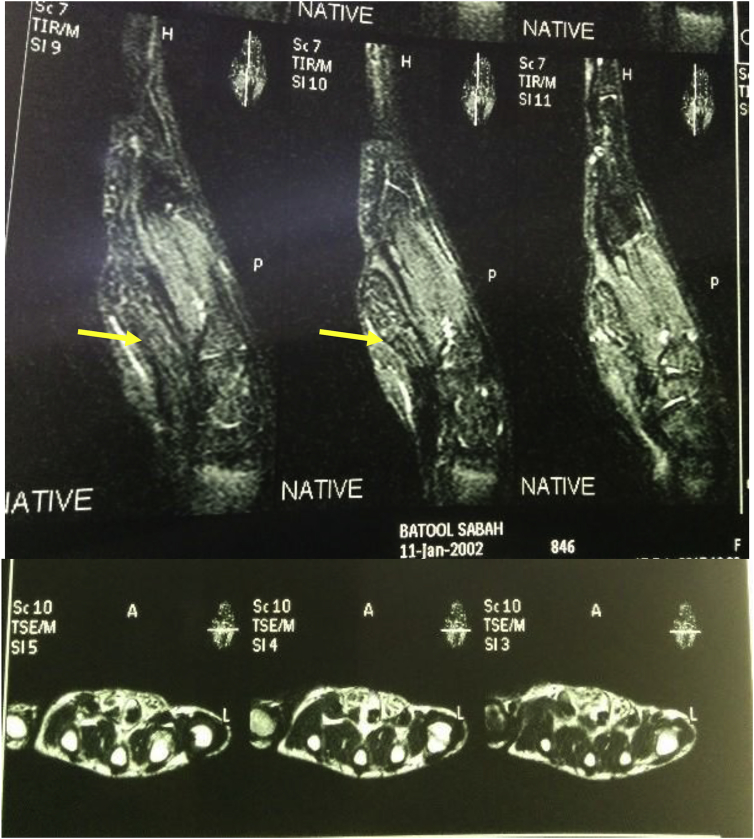

MRI reported hypertrophied non-enhancing fatty tissue of mid palm region along the tendon of flexor muscle and extend to the subcutaneous fat with macrodactyly of middle fingers, features suggestive of macrodystrophia lipomatosa (Fig. 2). With-out mentioning any point about median nerve. On these bases, surgical exploration was recommended.

Fig. 2.

Sagittal and axial section MRI, Enlarged cable like median nerve.

In LFH, perineurium and epineurium surrounding nerve branches become infiltrated by disproportionate amount of fibroadipose tissue, causing fusiform enlargement of the specific nerve14 and giving the typical MRI picture of coaxial cable appearance on axial view and spaghetti appearance on coronal and sagittal views.14